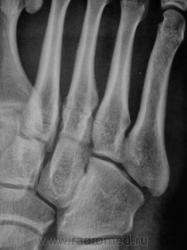

Травмы не было. Боли в переднем отделе стопы.

Но, юноша интенсивно занимается классической борьбой.

Так а как иначе, чем лоозеровские зоны перестройки.

А. может "стресс-переломом" обругаем...

Оно то конечно можно, дабы поумерить пыл борца на какое то время...по пока, по сути, это не перелом.